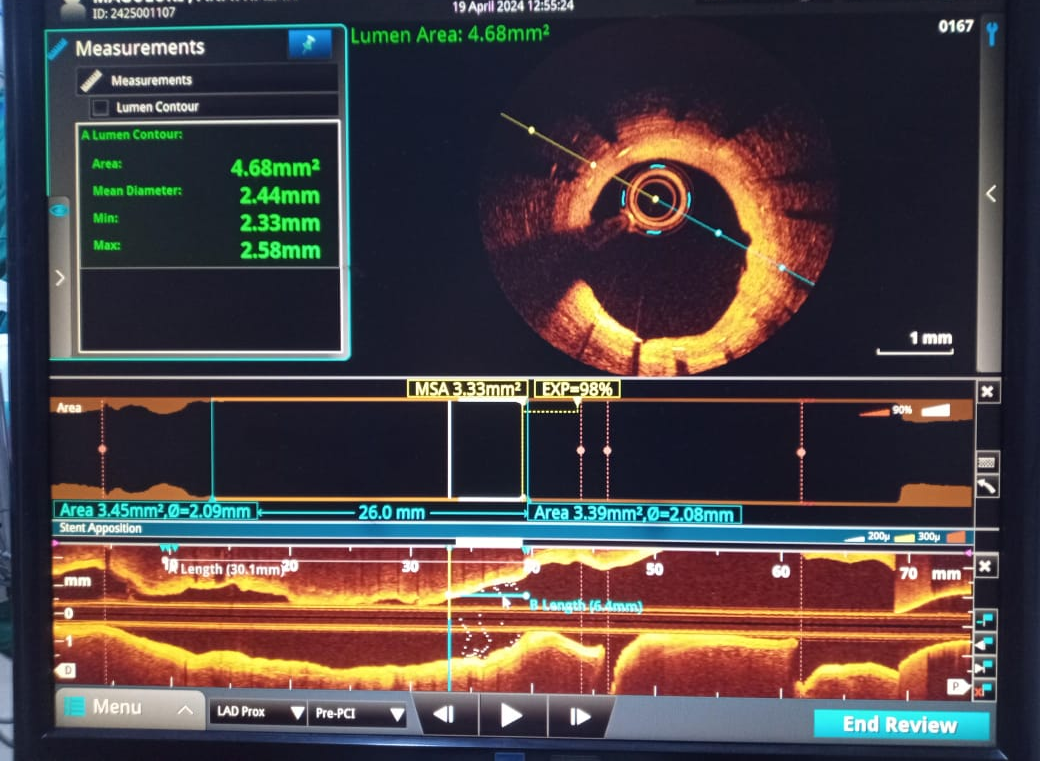

PCI was planned to LAD ISR lesion through right radial approach with 6 French sheath. Optical Coherence Tomography (OCT) was chosen for intracoronary imaging modality as it gives high resolution images to know the plaque morphology, exact mechanism of ISR which help in planning device selection and also to assess the adequacy of lesion preparation. 3.5 EBU 6 French Guiding catheter was taken with Runthrough (Terumo ,Japan) guidewire. Initial OCT ( Dragonfly OpStar catheter, Abbott,USA) run was done. Thick neointimal hyperplasia was seen with neoatheroma in mid portion of ISR lesion. mm as mean diameter in the distal reference segment was 2.9 mm (EEL to EEL) and the measured stent diameter was 2.6 mm. The MLA at the tightest point was 1.15 mm2 . Lesion length was 28 mm. We planned to do plaque modification with cutting balloon and correction of stent under expansion with non compliant balloon followed by drug coated balloon application.Initial plaque modification was done with wolverine (Boston Scientific,USA) 2.5 X 10 mm cutting balloon up to 12 atm from distal to proximal followed by 3.0 x12 mm NC Quantum Apex (Boston Scientific,USA) balloon inflation from 16 to 20 atm. Final OCT run was done which showed intimal micro tears with good lumen gain. 3x 30 mm Agent (Boston Scientific,USA) Drug-Coated Balloon was inflated within the lesion area at 6 atm nominal pressure for 90 seconds. TIMI 3 flow was seen with good vessel expansion on angiography.

Case Summary